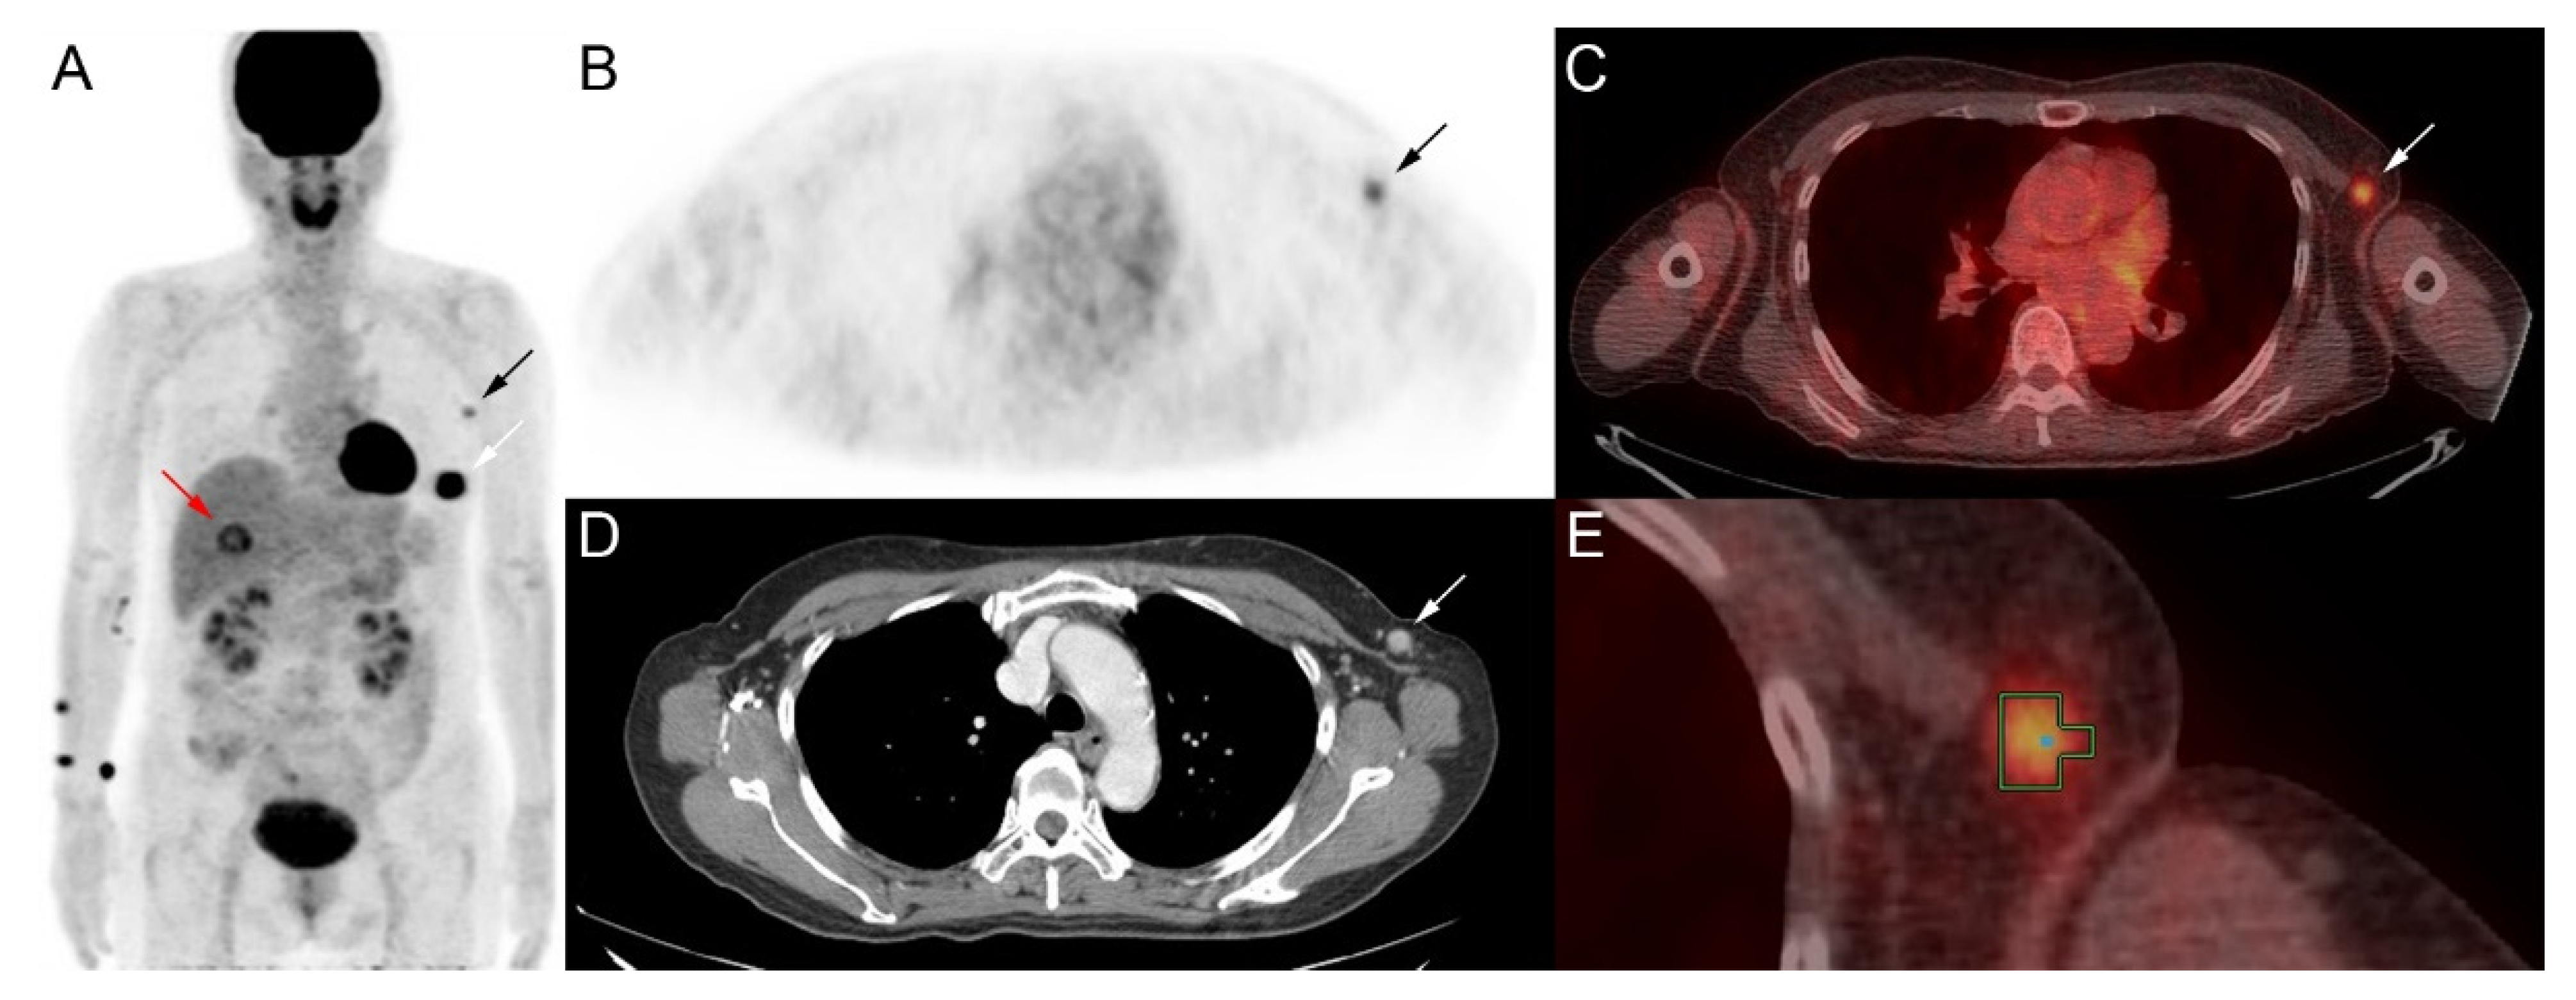

3.1. Image Analysis